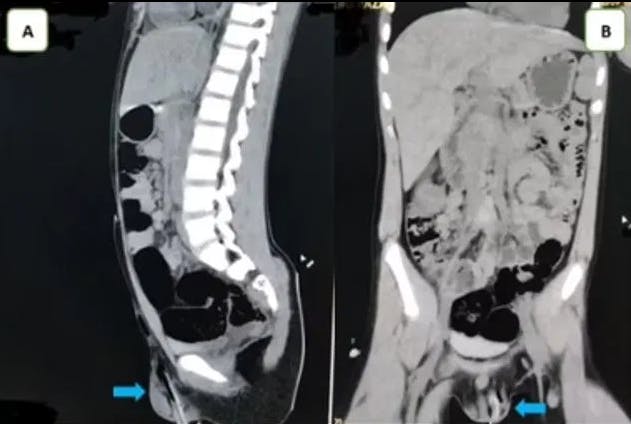

Drengen kom på hospitalet, hvor røntgenfotos, som er publiceret i Urology Case Reports, viser drengens uheldige, smertefulde og helt ufrivillige "intim-piercing".

Her viser røntgenbillederne, hvordan den fem centimeter lange gren har boret sig op gennem pungen og op mod kønsbenet.